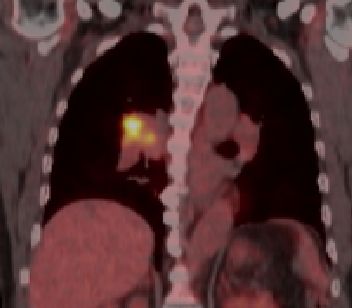

blauer Punkt 65mm großes Adenokarzinom des rechten Lungenoberlappens mit Infiltration der dorsalen Thoraxwand.